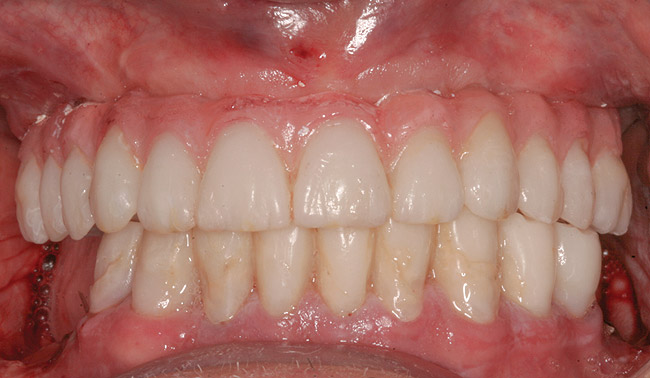

An important prosthetic consideration is knowledge of the appropriate implant position based on the type of restoration planned (cement- or screw-retained). Small variations in implant positions can lead to difficult restorative dilemmas. Accurate and predictable implant positioning using guided implant planning and placement can be critical to the esthetic and functional success of the restoration30 (Figure 8 through Figure 11).

Guided implant surgery involves reverse treatment planning. The ideal contour and arch position of the restoration is planned first, followed by virtual planning of the implant into that position according to the bony anatomy and clinical scenario. SLA surgical guides are then fabricated from the treatment plan. A dental laboratory next uses the SLA guide, with mounted casts, to fabricate provisional restorations prior to implant placement. At the time of surgery, the surgical guide is used to place the implants flaplessly, removing only a tissue core in the implant site(s). Abutments are immediately placed, and provisional restorations can be inserted.15-20 (Figure 12 through Figure 17).

Although technologies are available to place immediate definitive restorations, most clinicians are placing provisional restorations, for many reasons. Whether performed flaplessly or not, after surgery the final gingival contours and anatomy cannot be predicted. The clinician and dental technician can gain invaluable information as to the gingival contours and esthetics by observing tissue responses from the provisional restoration. Whether implant placement is guided or nonguided, a small number of implant failures occur. Most surgery-related failures take place within the first 3 to 4 months after implant placement. Surgical and restorative implant failure management is best accomplished prior to insertion of the definitive restoration. According to Abrahamsson et al, changing from a healing abutment to a permanent abutment did not result in a change in the dimension and quality of the transmucosal attachment that developed. It did not differ from the mucosal barrier that formed on a permanent abutment placed after surgery.31 An acrylic resin occlusal surface or a composite restoration reduces the forces of impact and has a better shock-absorbing behaviour compared to ceramic materials32; this is an additional reason for placing immediate acrylic resin provisional restorations, rather than immediate definitive porcelain restorations.

Figure 17  Provisional restoration placed at time of surgery.

Figure 17